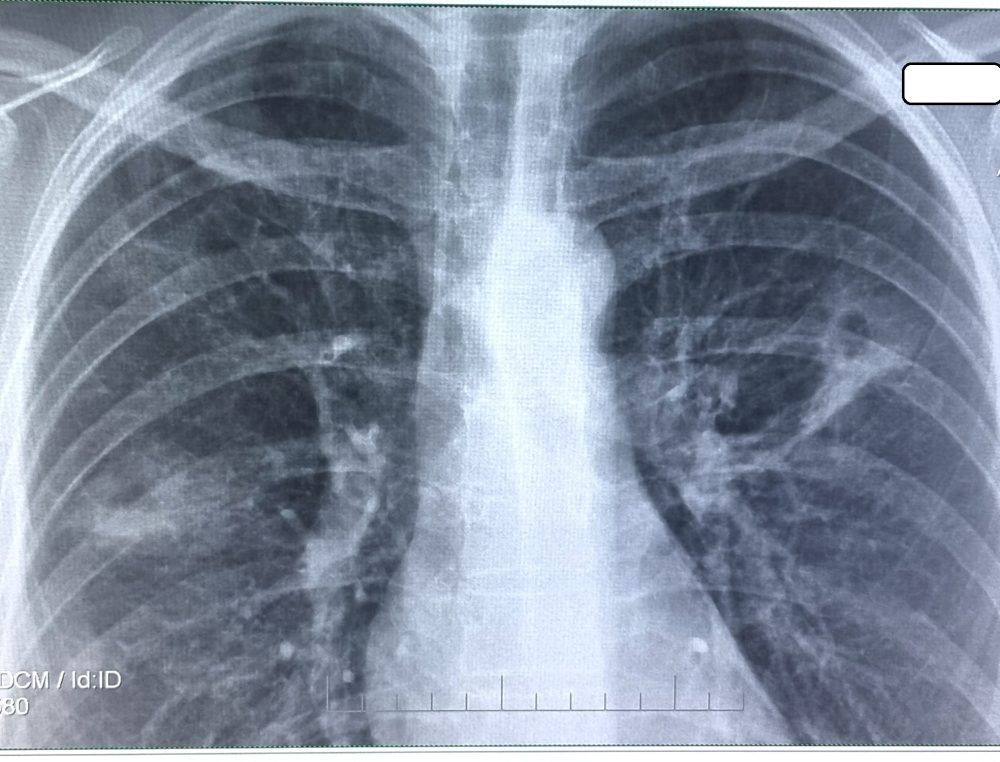

Boala afectează în principal plămânii, dar pot fi afectate şi alte organe (ganglioni, rinichi, coloană vertebrală, articulaţii, organe genitale, ochi, etc). Se transmite de la om la om prin strănut, tuse sau salivă, astfel că membrii familiei, prietenii sau colegii de muncă ai unei persoane cu tuberculoză se pot îmbolnăvi, la rândul lor. Din acest motiv, uneori, o persoană cu tuberculoză se poate simți stigmatizată și izolată de către anturaj, ceea ce poate cauza o suferință psihică, ce se adaugă celei cauzate de boală. Incapacitatea de a munci pe durata tratamentului până la vindecare poate cauza dificultăți materiale pacientului și familiei”, ne-a explicat dr. Marta Lefter.